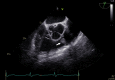

Decision-Making in a Pulmonary Valve Fibroelastoma: The Role of Intraoperative Transesophageal Echocardiography

Keywords: Cardiac fibroelastoma; Cardiac surgery; Cardiac tumor; Pulmonary valve; Transesophageal echocardiography.